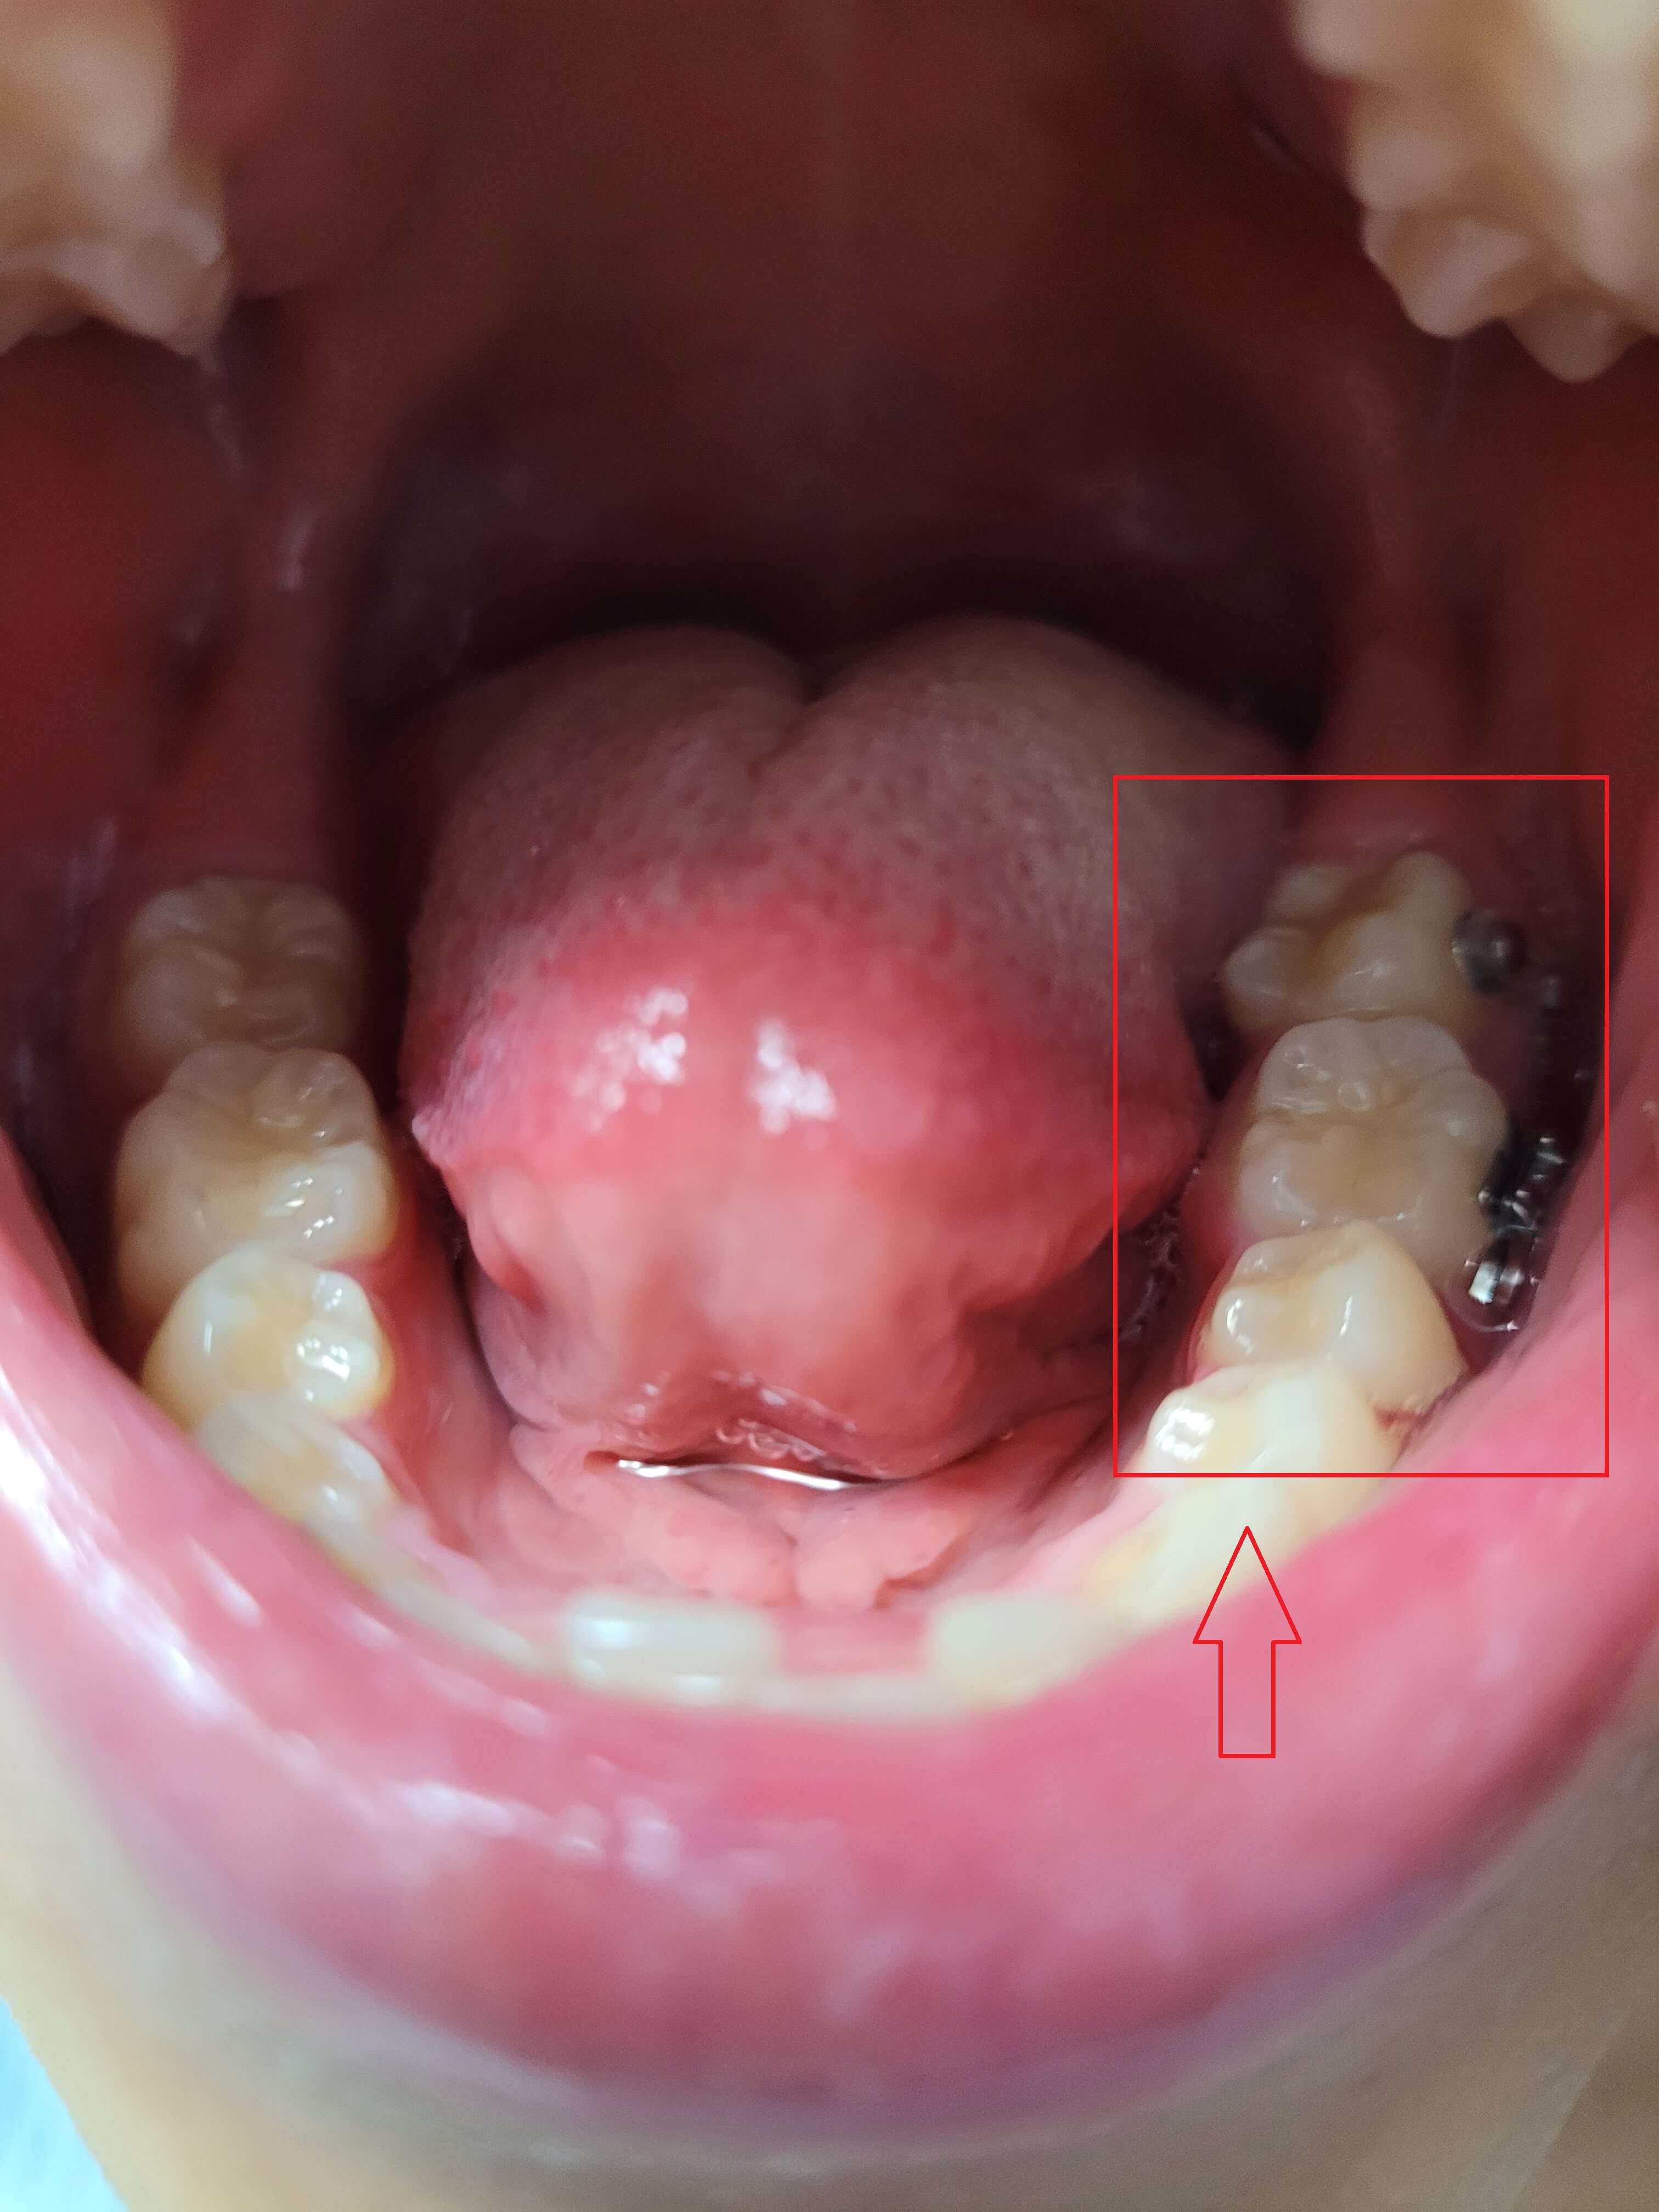

◎ 아들치아교정 전 상태확인 (가위교합사진)

- 「윗 어금니 가위교합 1개」

- 「아래 어금니 가위교합 1개」